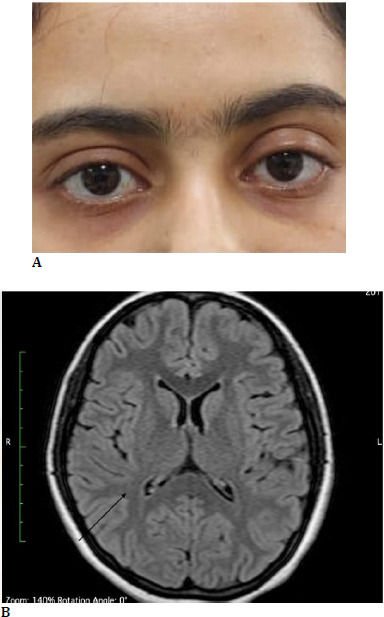

Case series: In the first case, a 36-year-old man came in with a left-sided headache and isolated third nerve palsy. Detailed investigations led to the discovery of a supraclinoid internal carotid artery aneurysm, necessitating prompt neurosurgical intervention. The second case featured a 74-year-old man with complete drooping of his right eyelid. The diagnosis of complete third nerve palsy led to further tests, which uncovered multiple myeloma. The third case involved a 19-year-old girl who had persistent double vision and bilateral ptosis. A collaborative effort between ophthalmologists and neurologists revealed Miller Fisher syndrome, which was successfully treated with intravenous immunoglobulins. Lastly, the fourth case described an 8-year-old girl who presented with optic neuritis. A thorough ophthalmological evaluation led to the diagnosis of Neuromyelitis Optica Spectrum Disorder, enabling early treatment and significant improvement.